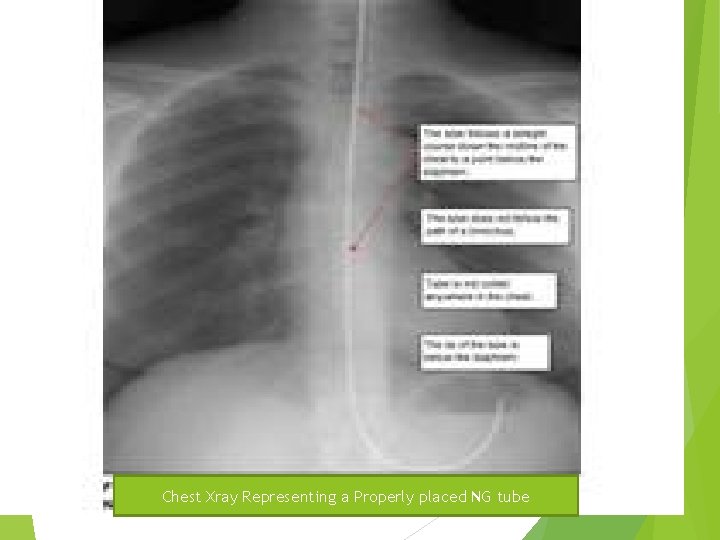

Nasogastric Intubation Insertion Procedures & Technique